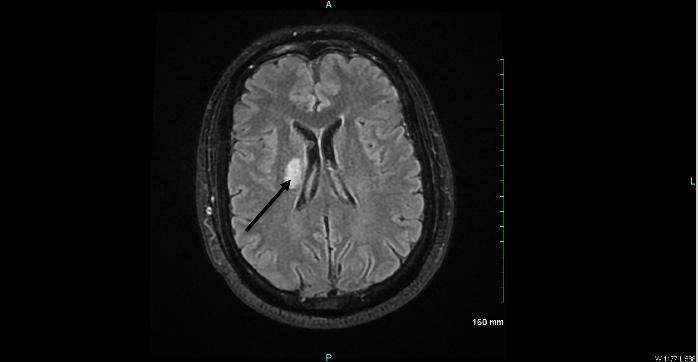

During her stay overnight, the rapid response team was activated for an acute mental status change, with last known well three hours prior. The patient was minimally responsive to pain with snoring respirations and a National Institute of Health Stroke Scale score of 22. On physical exam, the right pupil was 1 mm in diameter and reactive to light, and the left pupil was 4 mm and nonreactive. An emergent stroke workup was initiated, and CT angiography (CTA) of her head showed multifocal occlusions of the left posterior cerebral artery (PCA) (Image 1). The stroke neurologist communicated concerns for proximal basilar artery occlusion, and the patient was taken for emergent mechanical thrombectomy. Basilar tip occlusion was found. Thrombolysis in cerebral infarction grade 3 reperfusion was achieved after first pass, and the patient was admitted to the neurointensive care unit. The patient expired during her stay, which was complicated by development of aspiration pneumonia.

Image 2. Computed tomography angiography coronal view (Patient 2) with arrow pointing to the site of basilar artery occlusion with bilateral posterior cerebral artery involvement.